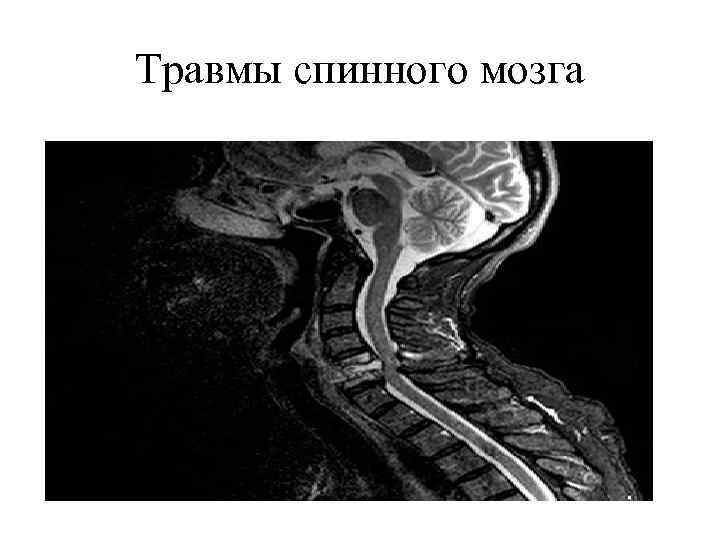

Травмы спинного мозга

Травмы спинного мозга